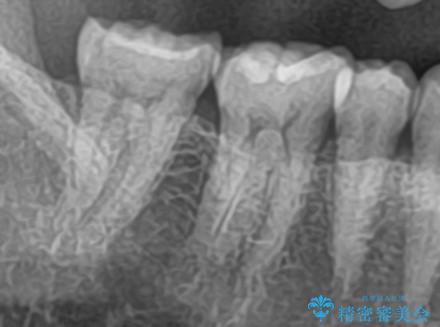

- 右下奥歯の詰め物が繰り返し欠けるとの主訴で来院されました。レントゲンとお口の中を詳細に診査した結果、以前の詰め物が咬み合わせの強い力に耐えきれず、また歯との適合も不十分であることが確認されました。患者様と相談し、今回は強度と耐久性に優れ、見た目も自然なセラミッククラウンで修復する治療計画を立案しました。これにより、再治療のリスクを減らし、長期的に安定した咬み合わせの回復を目指します。

治療では、まず古い詰め物を丁寧に取り除き、虫歯がないか確認しながら歯を丁寧に形を整えました。その後、精密な型取りを行い、患者様の歯の色や形に合わせたオーダーメイドのセラミッククラウンを作製しました。セラミックは天然歯のような透明感があり、非常に審美性に優れています。また、金属を使用しないため、金属アレルギーの心配もありません。